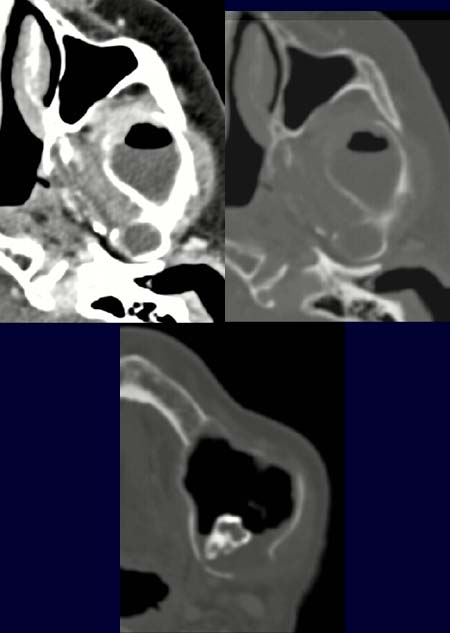

Im CT des Gesichtschädels kommt im Weichteilfenster nach Kontrastmittelgabe (linkes Bild oben) auf Höhe des Kieferwinkels eine Raumforderung zur Darstellung, teilweise mit und Flüssigkeit, teilweise mit Luft gefüllt. Zusätzlich kommt ventral eine Weichteilkomponente zur Darstellung.

Im Knochenfenster (rechtes Bild oben) ist die ventrale knöcherne Begrenzung teilweise nicht mehr nachweisbar.

Im Knochenfenster weiter kaudal (unteres Bild) kommt ein retinierter Zahn zur Darstellung.